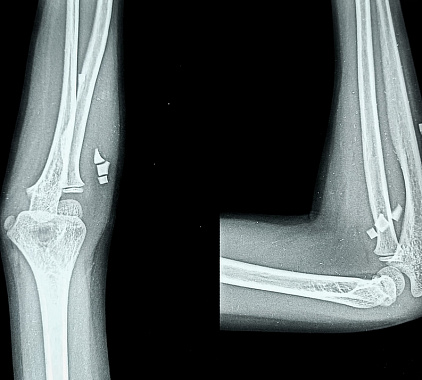

- Снимок в двух проекциях. Сначала прямой ракурс, затем боковой: предплечье сгибают под 90 , ладонь опускают вниз. Такая проекция раскрывает суставную щель, надмыщелки и венечный отросток.

- Тонкая просветляющая (радиопрозрачная) линия, проходящая через сустав. Линия свидетельствует о нарушении целостности костной ткани внутри сустава. Часто плохо визуализируется при стандартной проекции, поэтому рекомендуется дообследование с помощью КТ — это поможет точно оценить положение отломков и спланировать хирургическое вмешательство (например, остеосинтез).

- Неровный, «зазубренный» край локтевого отростка. Возможен мелкооскольчатый перелом. Наличие мелких отломков делает сращение сложным. Если кости неправильно срастутся, это может привести к ограничению подвижности и развитию посттравматического артроза. Необходим тщательный контроль восстановления.

- Спиралевидная линия перелома в диафизе локтевой кости. Возможен перелом Монтеджи. Серьезная травма часто сочетается с вывихом головки лучевой кости. Требует оперативного вмешательства — в противном случае возможна нестабильность сустава и нарушение функции предплечья.